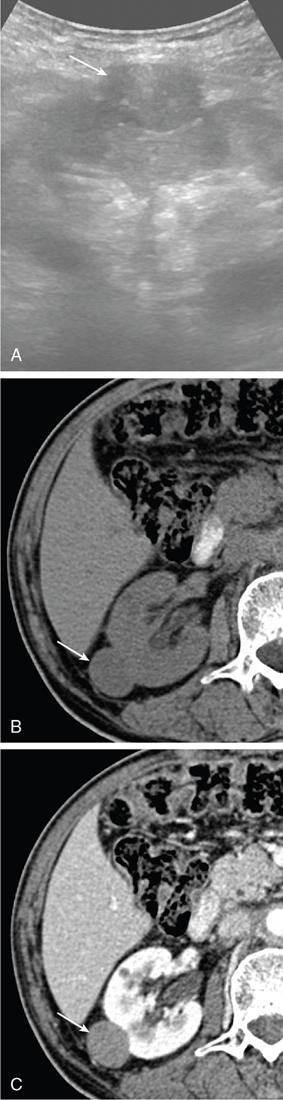

IMAGING OF RENAL MALIGNANCIES IN ADULTS Aparna Katdare, Palak Bhavesh Popat, Nilesh P. Sable, Ganesh Bakshi, Suyash Kulkarni Detection of renal masses has increased remarkably in recent times owing to wide-spread use of cross-sectional imaging. Imaging plays an important role in characterizing renal masses and is indispensable in treatment planning in renal malignancies. The most commonly encountered malignant renal masses in practice include renal cell carcinoma (RCC), urothelial carcinoma, lymphoma and metastases. Urothelial carcinoma and lymphoma have been covered in detail in separate chapters. RCC constitutes nearly 90% of all renal malignancies with a higher incidence in North America and Europe than India, Africa and China. With an increase in the number of cross-sectional studies performed, especially in Western population, the incidental diagnosis of RCC has increased in recent times, with such incidentally diagnosed lesions presenting at earlier stages with better prognosis and reduced rates of recurrence. The median age of presentation of RCC is 64 years according to the Surveillance, Epidemiology and End Results (SEER) program database and almost a decade earlier in Indian population, with a definite increasing risk of RCC with increasing age. Males are affected about 2–3.5 times more than females. In the Indian population, patients have been seen to present at a later stage as compared to the Western population. Amongst the various postulated risk factors, there is convincing evidence that smoking, hypertension, obesity and acquired renal cystic disease increase the risk of RCC. Alcohol intake and physical activity have been found to be associated with reduced risk of RCC. Trichloroethylene and cadmium exposure have been postulated as likely causes as well. Two to four per cent of RCCs are hereditary, with association of various genetic disorders such as Von Hippel Lindau (VHL) syndrome, hereditary papillary renal carcinoma, hereditary leiomyomatosis RCC, Birt-Hogg-Dube syndrome, chromosome 3 translocation and tuberous sclerosis (TCS1, TCS2). The WHO classification of 2016 (Table 11.25.1.1) stratifies tumours of the kidney into different subtypes based on cytoplasmic and architectural features, tumour location, background renal disease and molecular alterations. Clear cell renal cell carcinoma Multilocular cystic renal neoplasm of low malignant potential Papillary renal cell carcinoma Hereditary leiomyomatosis and renal cell carcinoma-associated renal cell carcinoma Chromophobe renal cell carcinoma Collecting duct carcinoma Renal medullary carcinoma MiT family translocation renal cell carcinomas Succinate dehydrogenase-deficient renal carcinoma Mucinous tubular and spindle cell carcinoma Tubulocystic renal cell carcinoma Acquired cystic disease-associated renal cell carcinoma Clear cell papillary renal cell carcinoma Renal cell carcinoma, unclassified Papillary adenoma Oncocytoma 8310/3 8316/1a 8260/3 8311/3* 8317/3 8319/3 8510/3a 8311/3a 8311/3 8480/3a 8316/3a 8316/3 8323/1 8312/3 8260/0 8290/0 Metanephric adenoma Metanephric adenofibroma Metanephric stromal tumour 8325/0 9013/0 8935/1 Nephrogenic rests Nephroblastoma Cystic partially differentiated nephroblastoma Paediatric cystic nephroma 8960/3 8959/1 8959/0 Clear cell sarcoma Rhabdoid tumour Congenital mesoblastic nephroma Ossifying renal tumour of infancy 8964/3 8963/3 8960/1 8967/0 Leiomyosarcoma Angiosarcoma Rhabdomyosarcoma Osteosarcoma Synovial sarcoma Ewing sarcoma Angiomyolipoma Epithelioid angiomyolipoma Leiomyoma Haemangioma Lymphangioma Haemangioblastoma Juxtaglomerular cell tumour Renomedullary interstitial cell tumour Schwannoma Solitary fibrous tumour 8890/3 9120/3 8900/3 9180/3 9040/3 9364/3 8860/0 8860/1a 8890/0 9120/0 9170/0 9161/1 8361/0 8966/0 9560/0 8815/1 Cystic nephroma Mixed epithelial and stromal tumour 8959/0 8959/0 Well-differentiated neuroendocrine tumour Large cell neuroendocrine carcinoma Small cell neuroendocrine carcinoma Phaeochromocytoma 8240/3 8013/3 8041/3 8700/0 Renal haematopoietic neoplasms Germ cell tumours The morphology codes are from the International Classification of Diseases for Oncology (ICD-O) {917A}, Behaviour is coded/0 for benign tumours; /1 for unspecified, borderline or uncertain behaviour; /2 for carcinoma in situ and grade III intraepithelial neoplasia; and /3 for malignant tumours. The classification is modified from the previous WHO classification (756A), taking into account changes in our understanding of these lesions. aNew code approved by the IARC/WHO Committee for ICD-O. Of these, the most common entity is the clear cell subtype, while papillary and chromophobe subtypes are less common. The different subtypes show varied biological behaviour, treatment response and prognosis. The 2017 guidelines by American Urological Association (AUA) as well as 2019 guidelines by European Society of Medical Oncology (ESMO) recommend multiphase cross-sectional imaging by either CT or MRI for renal mass characterization and staging. AUA 2017 guidelines recommend renal mass characterization on the basis of tumour complexity, contrast enhancement and presence or absence of fat. MRI has an upper hand over CT in characterizing subtle mass enhancement, cystic lesions and lesions less than 2 cm. ESMO recommends contrast-enhanced CT study of the chest, abdomen and pelvis for renal mass staging. Bone scan and brain CT or MRI can be considered if indicated by clinical or laboratory investigations. For characterization of renal masses, a multiphase CT or MRI study is recommended. CT study constitutes an unenhanced study followed by contrast injection and acquisition of corticomedullary phase at 40 seconds, nephrographic phase at around 100 seconds and delayed phase at around 5 minutes. MRI protocol includes T2-weighted single-shot fast spin-echo 2D sequences, axial T1-weighted 2D sequence with in-phase and opposed-phase gradient echo imaging, precontrast and postcontrast imaging with a 3D T1-weighted spoiled gradient recalled sequences in corticomedullary phase at 30 seconds, nephrographic phase at 100 seconds, 180–210 seconds and delayed phase imaging at 5 minutes and diffusion-weighted imaging with multiple b-values 0–50, 400–500 and 800–1000 s/mm2. The ACR White Paper on CT imaging of incidental renal mass recommends using the following descriptors for characterizing renal masses: Given the prognostic implications, it is worthwhile for radiologists to know the imaging features that may help discriminate between the common histological subtypes of RCC on various imaging modalities. This is the most common histological type of RCC, accounting for about 70% of cases. These are exophytic tumours with a heterogeneous appearance due to the presence of necrosis, intratumoural haemorrhage, cystic components with septations and calcific foci and hence have a more heterogeneous appearance on cross-sectional imaging than the other subtypes (Fig. 11.25.1.1). Necrosis is seen more often in larger masses and higher tumour grades (Fig. 11.25.1.2). On CT, depending on the tumour composition, these are seen as heterogeneous lesions, show marked contrast enhancement in the corticomedullary phase with washout on nephrogenic phase (Fig. 11.25.1.2). On MRI, these characteristically show high signal intensity on T2W sequences (Fig. 11.25.1.3). The presence of intracytoplasmic fat in the clear cells of the tumour is reflected in the loss of signal in opposed phase images on chemical shift imaging, which is seen in nearly 60% of these tumours. A pseudocapsule may be seen, which is best appreciated on T2-weighted imaging on MRI; the presence of a pseudocapsule has a high negative predictive value for perinephric extension (Figs. 11.25.1.3 and 11.25.1.4). Conversely, larger tumours with higher grades often have interrupted pseudocapsule and hence tend to be irregular, spread into the perinephric fat with renal vein and inferior vena cava (IVC) invasion (Figs. 11.25.1.5 and 11.25.1.6). On diffusion-weighted imaging, clear cell RCCs have been seen to have higher ADC values than nonclear cell RCCs, and lower-grade tumours have been seen to have higher ADC values than higher-grade tumours. The clear cell variant has worse prognosis than the papillary and chromophobe subtypes, presenting at a more advanced stage and being more likely to recur or metastasize (Fig. 11.25.1.7), with lower 5-year survival rates at 44%–69% as compared to 78%–92% for the other two. Papillary RCC comprises about 10%–15% of RCCs. These are slow-growing tumours and hence are well-marginated in contrast to clear cell RCC. As they are hypovascular, their enhancement on CT is significantly less than clear cell RCC (Fig. 11.25.1.8). These show characteristically low signal on T2W images on MRI (Fig. 11.25.1.9). Intracytoplasmic or macroscopic fat is less often seen on MRI imaging as compared to the clear cell variants. Larger tumours tend to be more heterogeneous (Fig. 11.25.1.10). These tumours may sometimes show cystic appearances, mural projections or blood degradation products. Calcifications are more common in papillary variants than clear cell RCC. Multifocality and bilaterality are also more common in these tumours than clear cell variants. These account for about 5% of RCCs. These are less aggressive, more homogeneous and hypovascular lesions than clear cell variants, with intensity of contrast enhancement on cross-sectional imaging being midway between clear cell and papillary variants. They show low to intermediate T2 signals on MRI. A characteristic feature is the presence of a central scar and spoke-wheel enhancement, the latter being a histopathological and imaging similarity between these tumours and oncocytoma (Fig. 11.25.1.11). Other subtypes of RCC are much less common but some may show distinct imaging findings. Multilocular cystic RCCs have excellent prognosis and lack mural nodules within the cystic components, unlike clear cell RCCs with cystic degeneration which show mural nodules. Collecting duct carcinomas, on the other hand, are aggressive tumours with poor prognosis and have medullary origin, and therefore appear similar to transitional cell carcinomas on imaging. Medullary RCCs are associated with sickle cell disease and sickle cell trait and are seen as infiltrating intracalyceal obstructive lesions with associated nodal disease. The imaging work-up of a suspected RCC is aimed at: Localized renal cancer is defined as a disease confined to the renal capsule and refers mainly to stage I and II disease. Nearly 70% of RCCs, especially the lower-stage lesions, are incidentally diagnosed on cross-sectional imaging. Also, amongst incidentally diagnosed renal lesions less than 4 cm in size, about 20% turn out to be benign on histopathology. Asymptomatic incidentally diagnosed small renal masses have an indolent course and better prognosis. Nephron-sparing surgery (NSS) has gathered momentum in recent years due to promising results and prognoses in small lesions. The 2017 AUA guidelines for localized renal masses describe restricted and well-defined indications for radical nephrectomy, bigger role of nephron-sparing procedures such as partial nephrectomy, tumour enucleation and thermal ablation, as well as increasing role for biopsy as well as active surveillance of such lesions. Hence, imaging findings in these lesions become critical in charting management of these patients. The imaging features of common histopathological subtypes of RCCs have already been discussed above. Signal intensity on T2W images and corticomedullary phase enhancement have been seen to be independent predictors of clear cell and papillary RCCs. Further, T2 signal homogeneity can be a predictor for slower growth rate. Hence, in general, multiparametric MRI studies have been shown to be effective in small renal mass characterization and can subsequently guide decisions regarding biopsy, surgery or surveillance. CT is a good alternative in patients with contraindication to MRI. For cystic renal lesions, the Bosniak classification, which stratifies the risk of neoplasia in cystic renal lesions based on the complexity of their appearance (wall thickness, septations, solid component), can be used effectively to decide further course of management. The Bosniak classification originally applies to CT findings but can logically be extrapolated to MRI, USG and Contrast Enhanced Ultrasound (CEUS) as well. Bosniak I and II cysts are benign while Bosniak IIF, III and IV cysts show progressively increasing risk of neoplasia. Given the more indolent course of cystic RCCs as compared to solid lesions and possible complications of interventions, lately there has been a case for even the type III and IV cysts, which previously would be operated, to be followed up, especially if patient has existing comorbidities or if the solid component is minimal. Initial follow-up would be at 6 months, followed by annual imaging. AUA 2017 guidelines recommend considering renal mass biopsy if haematologic, metastatic, inflammatory or infectious aetiology is suspected. Once the need for surgery is established in a localized disease, NSS may be considered for stage Ia and Ib disease. To predict perioperative outcomes in NSS, various scoring systems have been proposed for preoperative renal mass evaluation, such as R.E.N.A.L. nephrometry score, PADUA score (Preoperative aspects and dimensions used for anatomical classification), C-index method and mathematical tumour contact surface area (CSA). The popular R.E.N.A.L. nephrometry score takes into account various tumour descriptors that help decide the technical feasibility of NSS and predict surgical outcomes. These include tumour radius, exo/endophytic location, nearness to collecting system or renal sinus, anterior/posterior location and location with reference to polar lines. These descriptors need to be commented upon diligently while reporting renal masses (Table 11.25.1.4). Higher scores are seen to correlate with ischaemia time, postoperative urologic complications, higher grade and mortality. These include organ-confined tumours more than 7 cm in size, or tumours of any size which show regional nodal involvement and/or invasion of perinephric tissues but confined to Gerota’s fascia. These include renal vein and IVC invasion (luminal and mural). Generally, radical nephrectomy is recommended by the National Comprehensive Cancer Network (NCCN) in stage II and III RCCs. Both CT and MRI are effective in diagnosing locally advanced disease in RCC. The loss or interruption of pseudocapsule is seen in more infiltrative and aggressive disease and is best seen on MRI. Local infiltration may be in the form of contiguous spread to perinephric tissues or discrete deposits in perinephric fat (Fig. 11.25.1.15). IVC or renal vein invasion could be in the form of intraluminal thrombosis or invasion of the vessel wall and have implications on surgical approach and outcomes. Tumour thrombus can be distinguished from bland thrombus by confirming vascularity within the thrombus on imaging. Doppler evaluation, CEUS, CT and MRI can all be helpful for the same. MRI is better than other modalities for venous evaluation, especially for mural invasion and IVC invasion (Figs. 11.25.1.16 and 11.25.1.17). Right-sided tumours, anteroposterior IVC diameter of 2.4 cm or more at the level of renal hilum and complete IVC occlusion at this level are associated with higher risk of IVC resection. About 16% of patients with RCC have metastases at diagnosis and about 20%–30% of patients operated for local disease develop recurrence or metastases at a later date. The recurrent disease occurs most commonly within 3 years of diagnosis and uncommonly even later in young patients or large tumours. The most common sites of metastases from RCC are lungs, liver, bones, nodes, adrenals and brain. CT scan is the preferred modality for primary staging and surveillance for metastases because of its widespread availability and versatility for diagnosing bone and soft tissue lesions. MRI is preferred for looking for recurrence in postablative lesions, wherein these are seen as new enhancing lesions or show increase in the size of preexisting enhancing components. 18FFluorodeoxyglucose – Positron Emission Tomography (PET)/CT and PET/MRI may be helpful to look for metastatic disease as well. 18FSodium fluoride – PET/CT has been found to be better than CT and bone scan in detecting osseous metastases. RCC is a relatively radiation-resistant tumour, and treatment options tilt in favour of surgical procedures for localized and locally advanced diseases. For metastatic disease, post-risk assignment, the treatment has to be planned. Treatment can be offered as per size and the clinical stage.